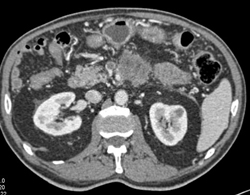

Cystic Mass of Pancreas